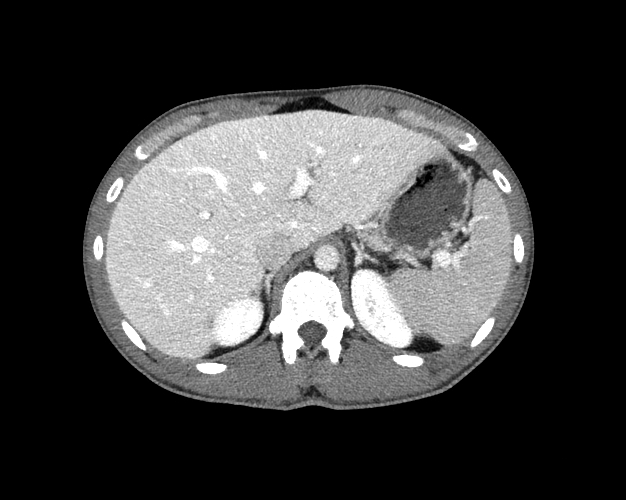

Body

Covers abdominal CT anatomy.